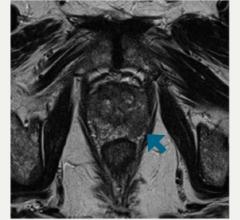

While active surveillance is often recommended for patients with nonaggressive prostate cancer to reduce unnecessary treatment, the challenge for clinicians is to monitor and distinguish early-stage tumors from advanced cancers.

Overlake Medical Center, Bellevue, Wash., recently announced it is formally adopting a new standard of care for prostate cancer treatment with the potential to dramatically decrease instances of over-treatment. The improvements are a result of magnetic resonance imaging (MRI) technologies to diagnose and guide biopsies to more accurately identify the cancer type and inform treatment.